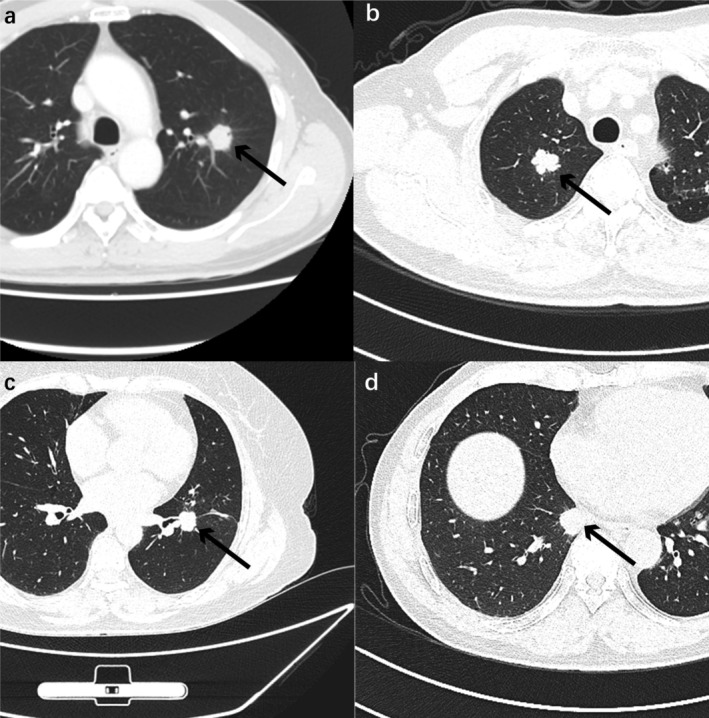

Results: The proportion of solid components (PSC), sphericity, nodule margin, entropy, and edge blur were identified as diagnostic factors that were strongly correlated with LNM in lung adenocarcinoma patients. The area under the ROC curve (AUC) in the internal training set was 0.91. Decision curve analysis revealed that the model could achieve greater benefits for patients. The calibration curve was used to further verify the applicability of the prediction model.

Conclusions: Patients with early-stage lung adenocarcinoma with LNM can be identified by typical imaging features. The diagnostic model can help to optimize surgical planning among thoracic surgeons.